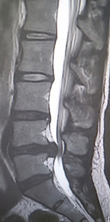

腰椎すべり症のX線とMRI。第4・5腰椎の間で前後に骨がずれて脊柱管が狭窄している。